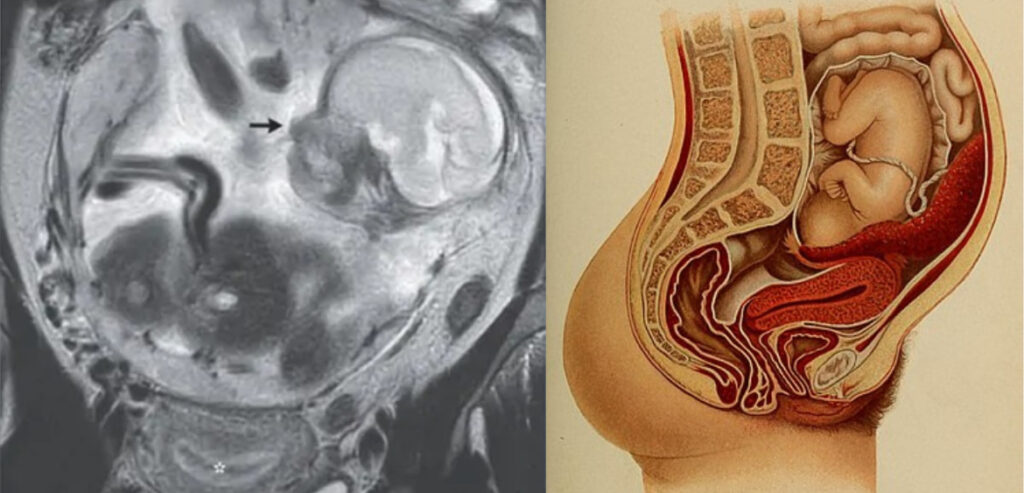

【ナゾロジー】子宮に胎児がいない?! 「腹腔で赤ちゃんを妊娠」した極めて稀なケースが報告される

1: すらいむ ★ 2023/12/18(月) 22:40:09.60 ID:t+GH/l3U 子宮に胎児がいない⁈ 「腹腔で赤ちゃんを妊娠」した極めて稀なケースが報告される ヒトの胎児は決まって、母親の子宮内部である「胎内」で育ちます。 しかし仏レユニオン大学病院センター(Le CHU ... -